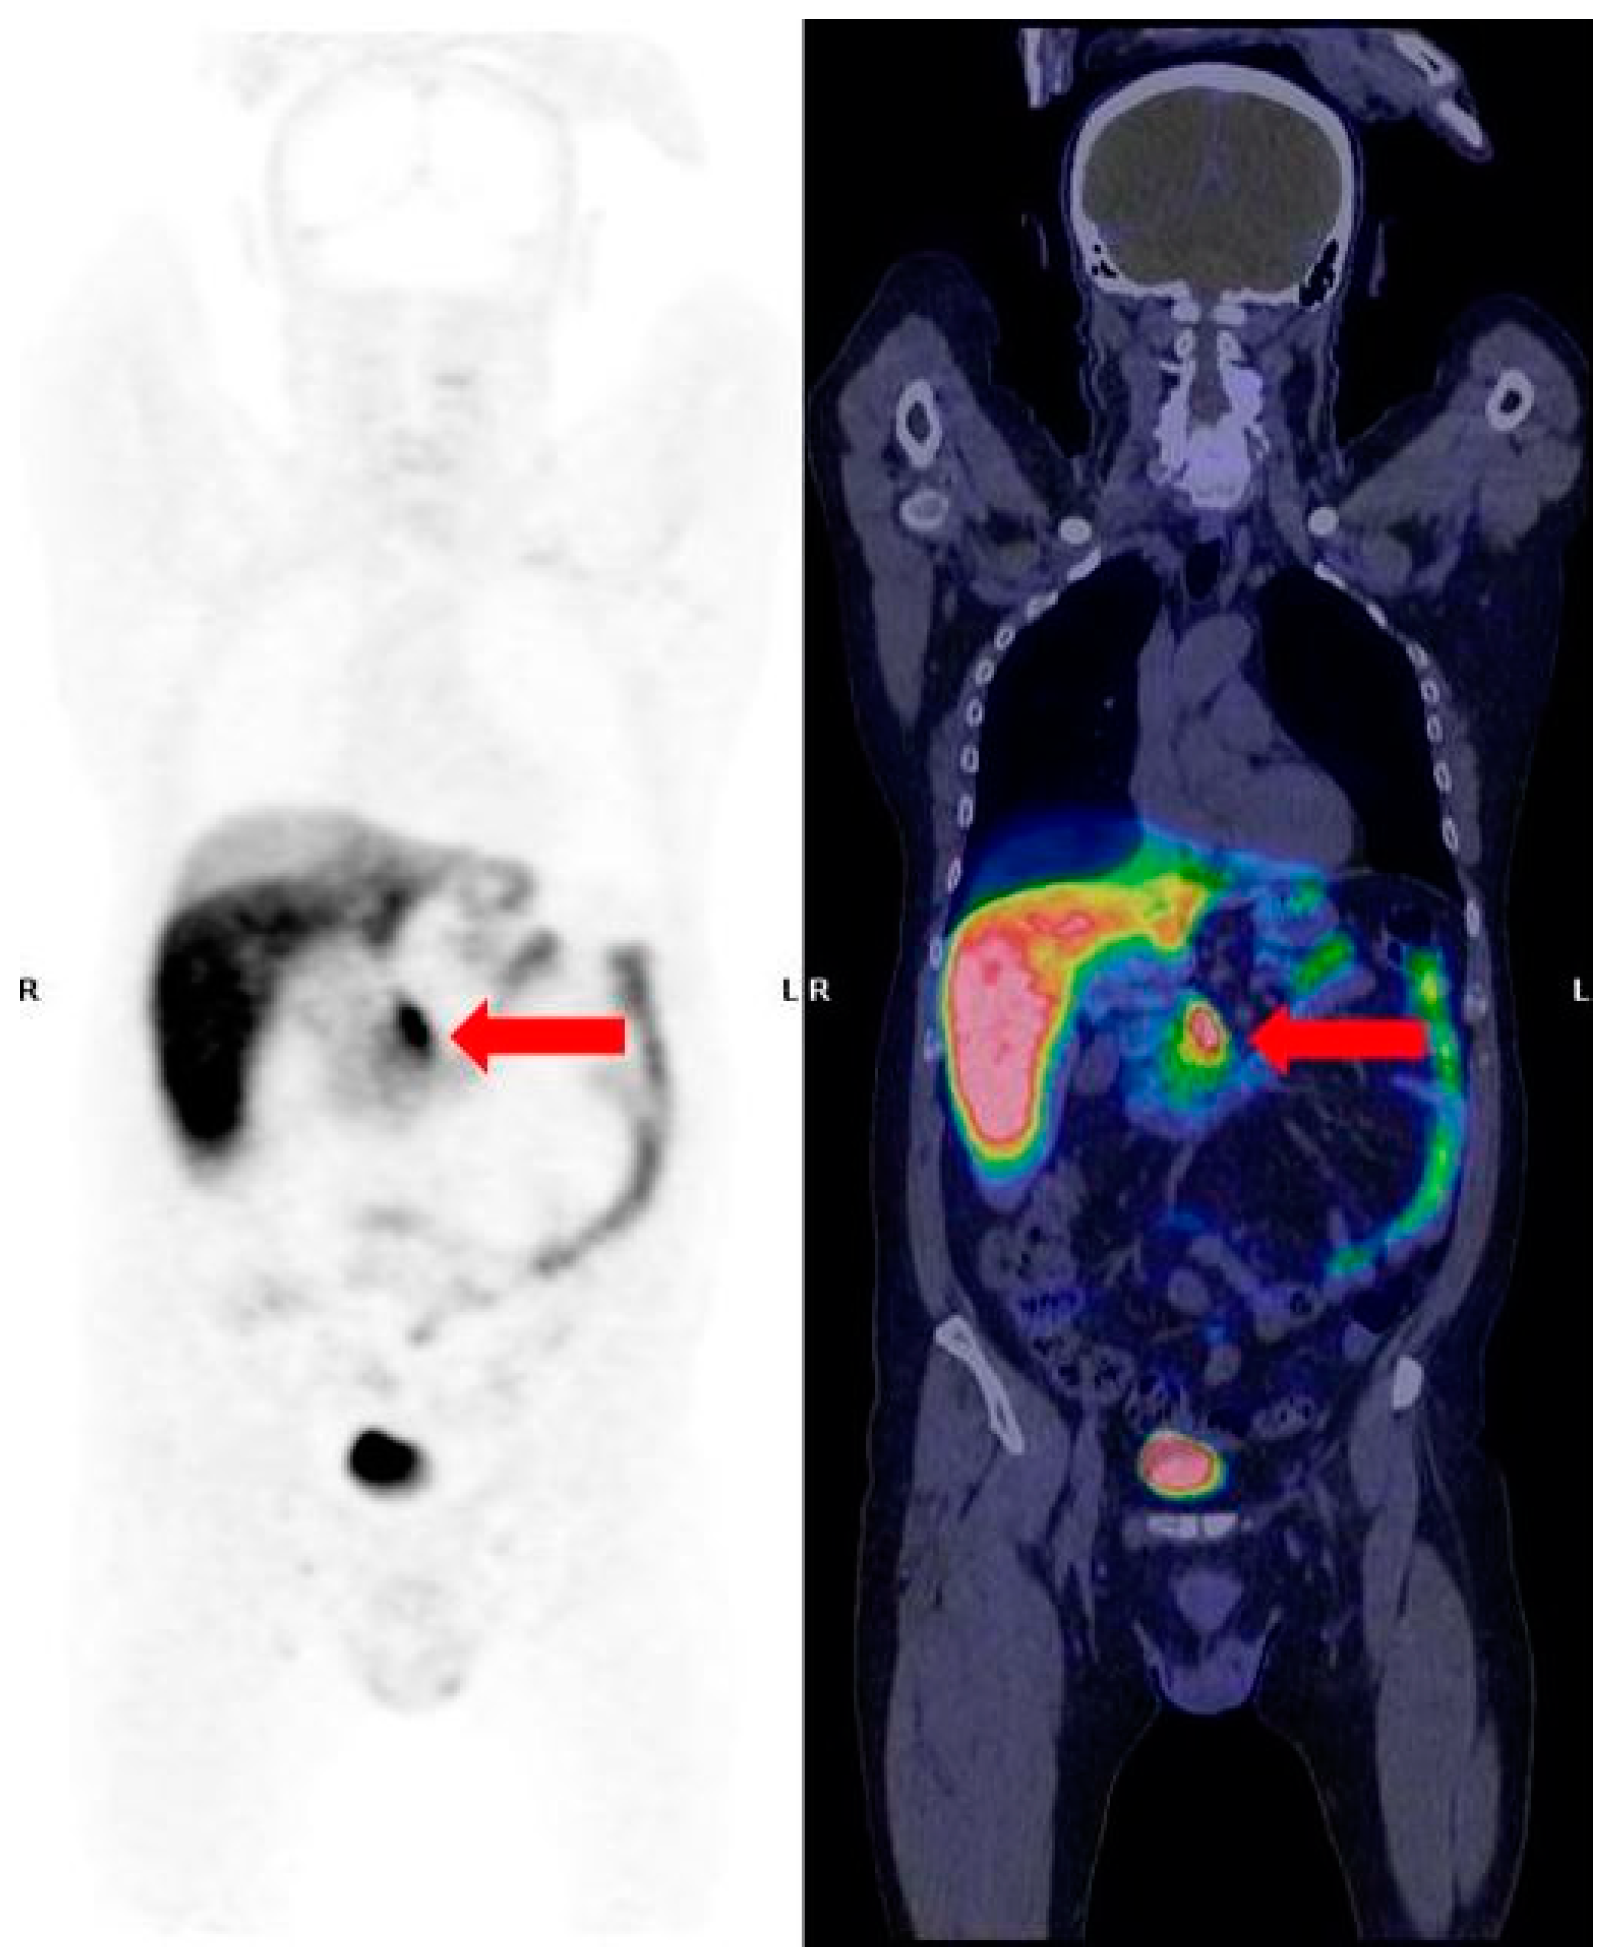

- Rinzivillo, M.; Partelli, S.; Prosperi, D.; Capurso, G.; Pizzichini, P.; Iannicelli, E.; Merola, E.; Muffatti, F.; Scopinaro, F.; Schillaci, O.; et al. Clinical usefulness of 18F-fluorodeoxyglucose positron emission tomography in the diagnostic algorithm of advanced entero-pancreatic neuroendocrine neoplasms. Oncologist 2018, 23, 186–192. [Google Scholar] [CrossRef]

- Cingarlini, S.; Ortolani, S.; Salgarello, M.; Butturini, G.; Malpaga, A.; Malfatti, V.; D’Onofrio, M.; Davì, M.V.; Vallerio, P.; Ruzzenente, A.; et al. Role of combined 68Ga-DOTA-TOC and 18F-FDG positron emission tomography/computed tomography in the diagnostic workup of pancreas neuroendocrine tumors. Pancreas 2017, 46, 42–47. [Google Scholar] [CrossRef]

- Carideo, L.; Prosperi, D.; Panzuto, F.; Magi, L.; Pratesi, M.S.; Rinzivillo, M.; Annibale, B.; Signore, A. Role of Combined [68Ga] DOTA-SST Analogues and [18F] FDG PET/CT in the Management of GEP-NENs: A Systematic Review. J. Clin. Med. 2019, 8, 1032. [Google Scholar] [CrossRef] [PubMed]